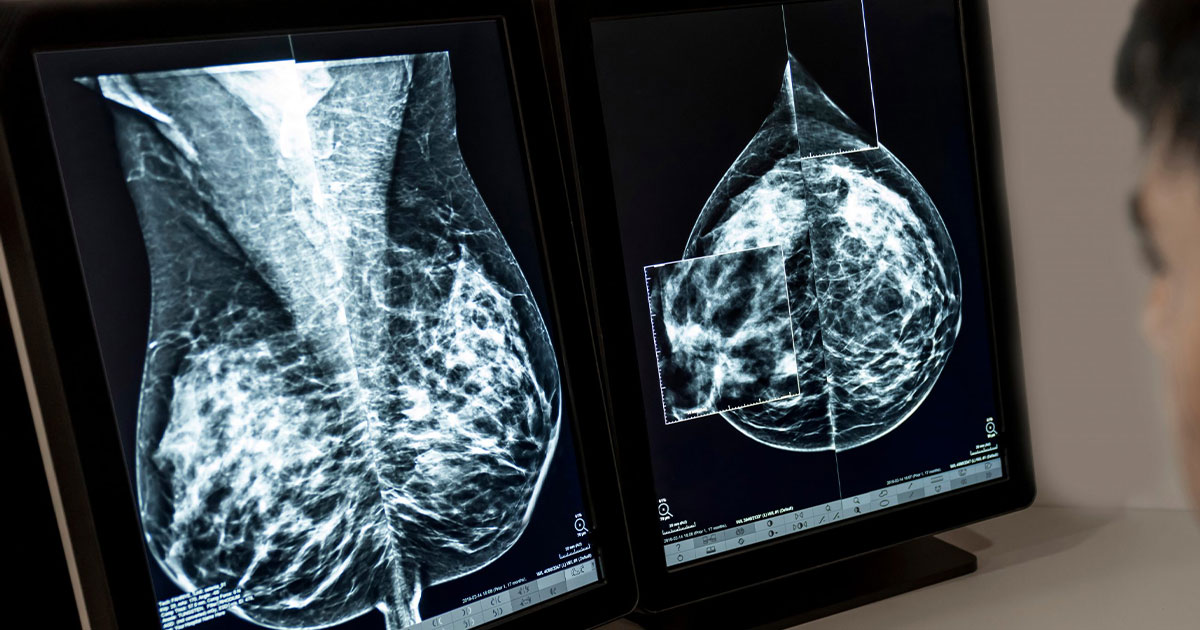

وفي إطار السعي لسد فجوة الكشف المبكر وتحسين دقة التشخيص، تكشف النتائج الأولية لهذا الفريق البحثي عن نموذج متطور للذكاء الاصطناعي -يعتمد على تحليل صور الماموجرام فقط- قادر على التنبؤ بخطر الإصابة بسرطان الثدي خلال السنوات الخمس المقبلة بدقة تفوق الأساليب التقليدية بكثير، خاصة تلك التي تعتمد على كثافة نسيج الثدي وحدها.

ويتميَّز هذا النموذج بقدرته على التقاط أنماط دقيقة في أنسجة الثدي لا يمكن لمختصي الأشعة رؤيتها بالعين المجردة، مما يتيح تصنيفًا أدق وأكثر وضوحًا لمستويات الخطر بين النساء.

وأوضح الفريق البحثي أن نموذج الذكاء الاصطناعي يمتلك القدرة على رصد تغيرات دقيقة في أنسجة الثدي لا يمكن للعين البشرية ملاحظتها، الأمر الذي يجعله نقلة نوعية في مستوى التحليل الطبي؛ لأنَّ هذا النموذج يفتح آفاقًا جديدة لاستخدام المعلومات الخفية داخل الصور الإشعاعية -تلك التي لم يكن بالإمكان استغلالها بالطرق التقليدية- ولا يكتفي بتحسين دقة التشخيص، مما يعكس التطور الكبير الذي صار الذكاء الاصطناعي يقدمه في المجال الطبي وتحسين كفاءة الخدمات الصحية وجعلها أكثر استدامة.

وُضع نموذج الذكاء الاصطناعي أمام اختبار به مجموعة واسعة تضم أكثر من236 ألف صورة ماموجرام ثنائية الجانب من خمسة مراكز طبية في الولايات المتحدة، بالإضافة إلى8,810 صورة من مركز أوروبي واحد. وقد جُمعت بيانات كثافة الثدي التي يحددها مختصو الأشعة (ثدي كثيف مقابل ثدي غير كثيف)، إلى جانب نتائج الإصابة بسرطان الثدي خلال خمس سنوات، اعتمادًا على السجلات الطبية وسجلات الأورام.